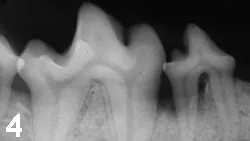

Local tissue may appear normal despite underlying disease, defining the need for periodontal probing and radiography (Figures 3-5).

Figure 4: Radiograph of the right mandible of the patient in Figure 3. Bone loss is evident surrounding the roots of the fourth premolar. The patient was observably more active after surgery to correct the defect.